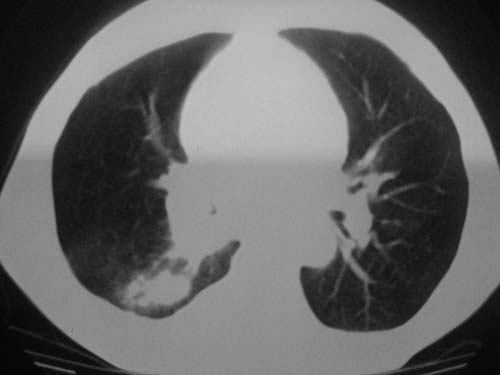

以下是引用科室第一人在2010-3-25 20:30:00的发言:[br]1:纵膈肿瘤性病变,恶性胸腺瘤可能性大伴纵膈右肺门淋巴结转移,右侧胸腔积液。[br]2:右侧肺门肿瘤性病变,纵膈淋巴结转移,右侧胸腔积液。右下叶转移。

以下是引用子期在2010-3-25 21:00:00的发言:[br]先考虑右中央型肺癌伴转移。

以下是引用江广1996在2010-3-25 22:49:00的发言:[br]通常肺癌向纵隔转移多见,纵隔肿瘤向肺内转移少见(有的表现为向肺内侵润)。本例以一元论考虑:右中心型肺癌并纵隔淋巴等多处转移。[br][br][本贴已被 江广1996 于 2010-3-25 22:50:07 修改过]

以下是引用yangyudong333在2010-3-26 6:43:00的发言:[br]“冰冻纵膈”,考虑纵膈淋巴瘤伴肺内及胸膜侵润。